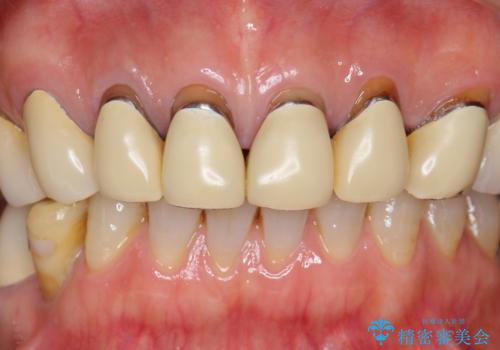

- 前歯のセラミック治療から4年半経過した患者様です。

4年ぶりに来院して下さいました。

治療した上の前歯6本は全く問題なく、「獅子舞みたいだった前歯を綺麗にして下さってありがとうございました!」と再度お礼を言って下さいました。

4年半前のクラウン装着時と変わらず、まるで天然歯のように自然に見えました。

患者様の良好なセルフケアと精密な適合の良いクラウンにより、歯肉の腫脹や退縮も認められませんでした。

エコノミーのオールセラミッククラウンに用いられるe-maxはニケイ酸リチウムガラスを主成分にしたセラミックです。

ガラスで出来ていることから非常に透明感があり、審美性と耐久性(強度はジルコニアの方が高い)を兼ね備えた材質です。

(強度 e-max:約400mPa、ジルコニア:900~1200mPa)

クラウンの種類:オールセラミッククラウン エコノミー